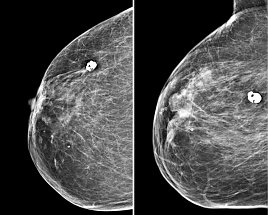

Die Mammografie ist ein Röntgenverfahren, das unter der Nutzung der charakteristischen Strahlung Schwächungsbilder der Brustdrüse erstellt, was üblicherweise in 2 Ebenen erfolgt (sog. CC und MLO-Aufnahme). Die Nutzung direkt-digitaler Systeme ermöglicht hier eine substantielle Reduktion der Strahlendosis von bis zu 40% im Vergleich zu Geräten, die erst im Nachgang ein digitales Bild erstellen oder analog verbleiben. Wir haben ein selenbasiertes Mammografiegerät in der Anwendung als einzigem entsprechend hochwertigen System in Nordthüringen und können so sehr dosissparend arbeiten. Außerdem sind bei uns 4 Röntgenassistenten nach entsprechenden Kursen als Mammafach-MTRA zertifiziert. Wir sind Partner verschiedener Brustzentren und führen im Jahr ca. 1500-2000 Mammografien durch im stationären und ambulanten Bereich. Alle Frauen mit einem Überweisungsschein und einer entsprechenden Indikation (beispielsweise einem Tastbefund oder einseitigen Schmerzen). Ein Mammakarzinom kann als Verdichtung strahlenförmig imponieren, aber auch als vielgestaltig gruppierter Mikrokalk (polymorpher Mikrokalkcluster) sowie in seltenen Fällen als Architekturstörung (siehe Beispielbilder). Ergänzend zu einer Befundung durch 2 Radiologen werden bei uns auch computerunterstützende Systeme verwandt, um eine zusätzliche Analysemöglichkeit zu entwickeln. Über diese Problematik wurden schon zahlreiche Publikationen von Prof. Malich verfasst.